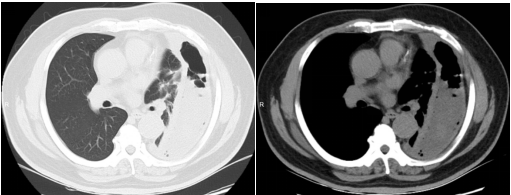

入院时CT显示:左侧胸腔被积液填满,如同一个巨大的"脓袋"压迫着正常肺组织。

棘手的是,传统穿刺引流如同"抽丝剥茧",抽出近2000ml腥臭脓液后,复查CT仍见残留大量纤维分隔包裹,配合强力抗生素治疗,患者仍然持续高烧不退。

历经4小时鏖战,手术团队成功拆除"定时炸弹"。术后第二天,患者体温即开始逐渐下降,后续继续全身应用抗生素、胸腔灌注药物、控制血糖、营养支持等综合治疗,患者病情迅速好转,复查肺CT恢复良好,患者对治疗效果表示满意。